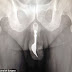

Doctors have removed a 10cm long steel fork from inside a man’s penis, after a sexual adventure went horribly wrong.

The 70-year-old man had visited Canberra Hospital’s emergency department complaining of bleeding genitalia.

He then promptly admitted that he had inserted a piece of cutlery into his urethra in an attempt to

pleasure himself.

Unfortunately the attempt backfired and the fork became stuck, leaving him in considerable pain. Despite this, it took him 12 hours to pluck up the courage to seek medical help.

The fork was so firmly lodged inside the man's body that doctors could not initially see the cause of the discomfort, according to the report in The International Journal of Surgery.

However, once it had been located, ‘multiple retrieval methods were contemplated with success achieved via forceps traction and copious lubrication.’

The procedure was successful and the elderly man was sent home with no long-term damage.